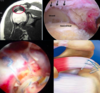

- Numerous ways to get the shoulder reduced: see attached images